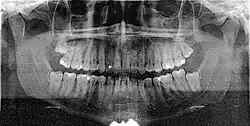

Jest to zdjęcie przeglądowe przedstawiające ogólny stan wszystkich zębów, zawiązków zębów oraz struktur je otaczających takich jak kości szczęki i żuchwy, stawy skroniowo-żuchwowe i częściowo zatoki szczękowe, jest również pomocne w ocenie wad rozwojowych[1], urazach i nowotworach.

Za pomocą pantomogramu można wykryć wiele nieprawidłowości, jak np. próchnica, zmiany okołowierzchołkowe, zęby zatrzymane, dodatkowe i nadliczbowe, zęby nieprawidłowo przeleczone kanałowo. Ze względu jednak na ogólny obraz czasami wymagane jest wykonanie dodatkowo dokładniejszego zdjęcia zębowego podejrzanej okolicy. Pantomogram daje również pogląd na stan kośćca w przypadku planowania zabiegu wszczepiania implantów zębowych – jednak w tym wypadku najczęściej korzysta się z tomografii komputerowej.